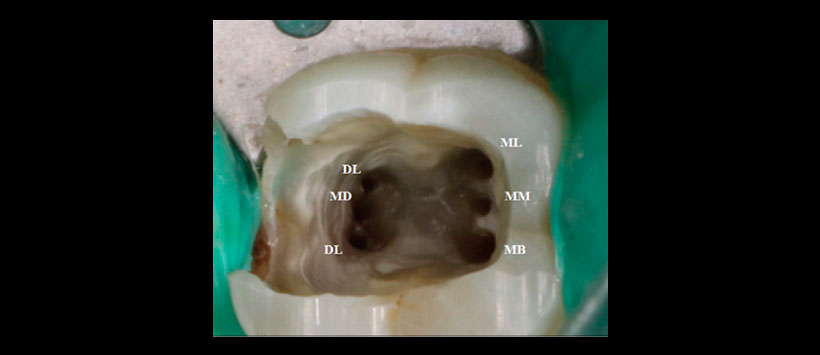

Figura 2: Fotografía de la abertura de acceso que muestra orificios de seis canales separados – DB: Distobucal, DL: Distolingual, MB: Mesiobucal, MD: Medio distal, ML: Mesiolingual y MM: Medio mesial.